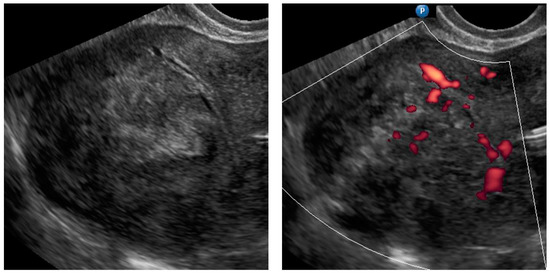

| Case Number (Age, Years Old) | Ultrasound Diagnosis of Uterine Lesion | Figure | Initial Treatment/ Histological Diagnosis Required (Doctor’s Decision) | Initial Patient’s Willingness to Undergo Surgery for the Uterine Lesion | Histology from Core Needle Biopsy | Patient Decision to Undergo Surgery for the Uterine Lesion | Histology from Definitive Surgery | Did Core Needle Biopsy Provided Additional Information to Ultrasound | Did Core Needle Biopsy Provided Useful Information for the Clinical Management |

|---|---|---|---|---|---|---|---|---|---|

| 1 (44) | Typical uterine lesion (myoma) | Figure A1 | No | Yes | Leiomyoma, cellular variant (UG-TUC core needle biopsy) | Yes (lesion enlarged during follow-up) | Leiomyoma, cellular variant | No | Yes |

| 2 (36) | Sarcoma suspicion | Figure A2 | Yes | Tumorectomy, uterus preservation (young age) | LMS (UG-TUC core needle biopsy) | Yes | LMS | No | Yes |